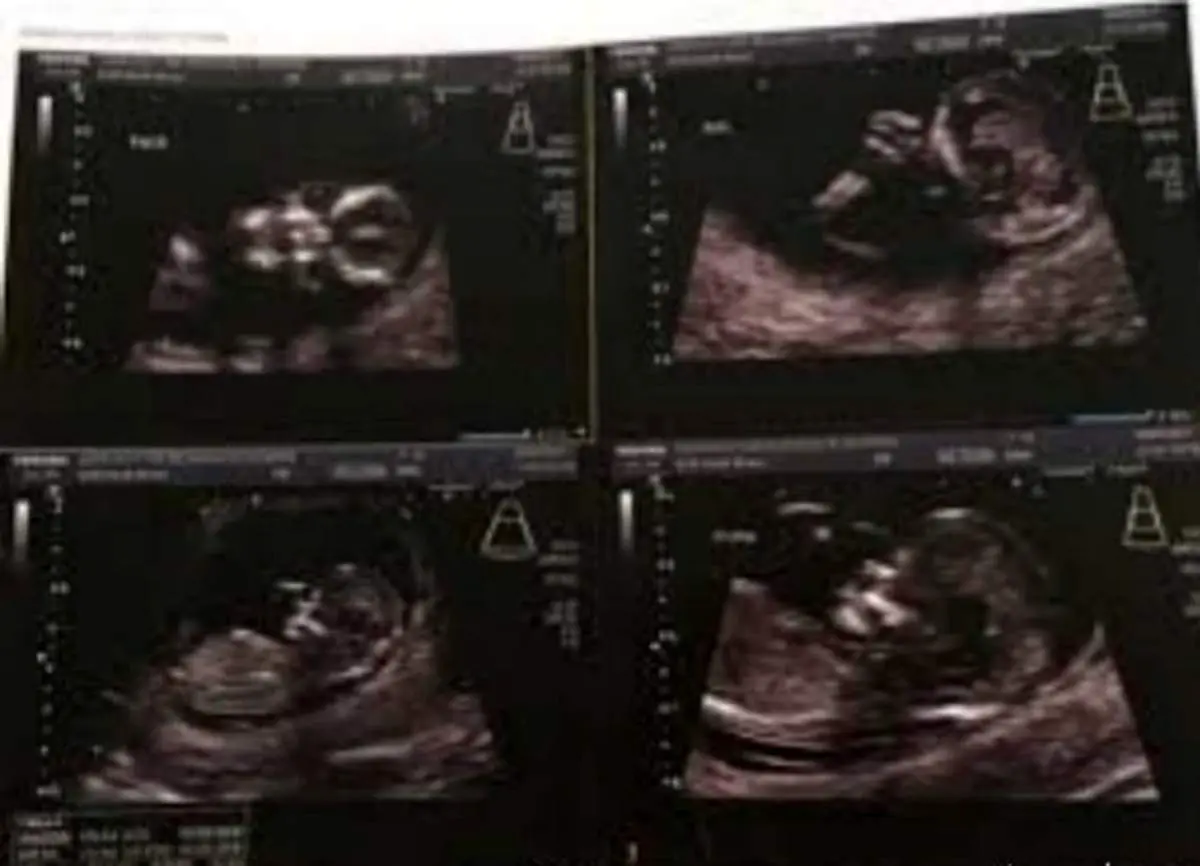

دیدن اولین عکس از جنین نه تنها برای "شارنی تونر" خوشایند نبود بلکه موجب شد تا شوکه شود."شارنی" اهل استرالیا عکس عجیبی از سونوگرافی جنینش را به اشتراک گذاشت و از ترس خود با دیدن آن برای اولین بار نوشت ، تصویری که بازدید بسیاری دریافت کرد و 31000 لایک گرفت.

عکس به اشتراک گذاشته شده که در این بخش مشاهده می کنید جنین را به شکل یک جمجمه عجیب انسان نشان می دهد ، حالتی واقعا ترسناک و شوکه کننده که با واکنش های منفی بسیاری روبرو شد اما مادر جوان اعلام کرده است که قصد سقط جنین ندارد و او را تا ماه نهم در شکم خود نگاه خواهد داشت.